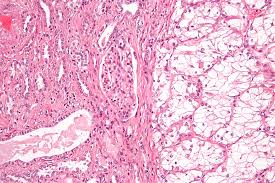

Blood in your urine this is the most common symptom and typically the earliest sign of kidney cancer. The urine typically appears to be deep red or rusty in color). Kidney cancer usually doesn't have signs or symptoms in its early stages. About 90 percent of kidney cancers are renal cell carcinomas, which originate in the tubules that transport waste materials from the blood to the urine. In other cases, the cause of a symptom may be a different medical condition that is not cancer. While a healthy diet can lower the risk of developing certain cancers, other factors like genes. Kidney cancer symptoms in women over 50. Blood in your urine this is the most common symptom and typically the earliest sign of kidney cancer. Typically, the symptoms occur in the latter stages of the disease. Dry and itchy skin can be a sign of the mineral and bone disease that often accompanies advanced kidney disease, when the kidneys are no longer able to keep the right balance of minerals and nutrients in your blood. The most common symptoms tend to show up in the lower back area or are evident in urine. In time, signs and symptoms may develop, including: Although kidney cancer is relatively more common in men, but this doesn't mean that kidney cancer is a male disease.